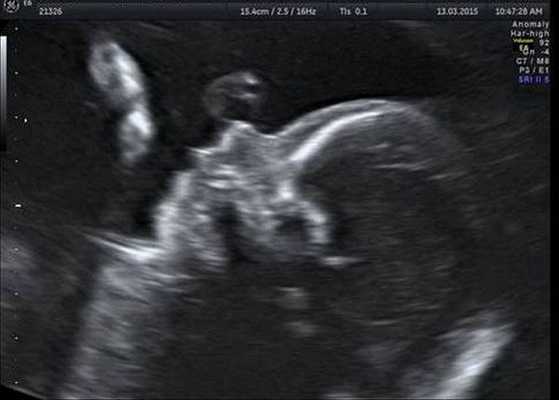

Прогноз при синдроме Гольденхара благоприятный, лечение заключается в косметической коррекции, слухопротезировании при возможности. Данное заболевание не наследуется. Существуют данные, что развитие синдрома Гольденхара связано с болезнью матери во время беременности на малых сроках, описаны случаи, связанные с острыми респираторными заболеваниями, ветряной оспой, гриппом. Возможна пренатальная диагностика заболевания при помощи ультразвукового исследования. При подозрении на синдром Гольденхара обязательно проводится исследование кариотипа для исключения фенокопий. Патогенез заболевания связан с нарушением формирования первой и второй жаберных дуг в процессе эмбриогенеза под воздействием, предположительно, внешних факторов.

Индивидуальная профилактика синдрома предполагает проведение медико-генетического консультирования семьи и пренатальной ультразвуковой диагностики беременной женщины в установленные сроки [12] .